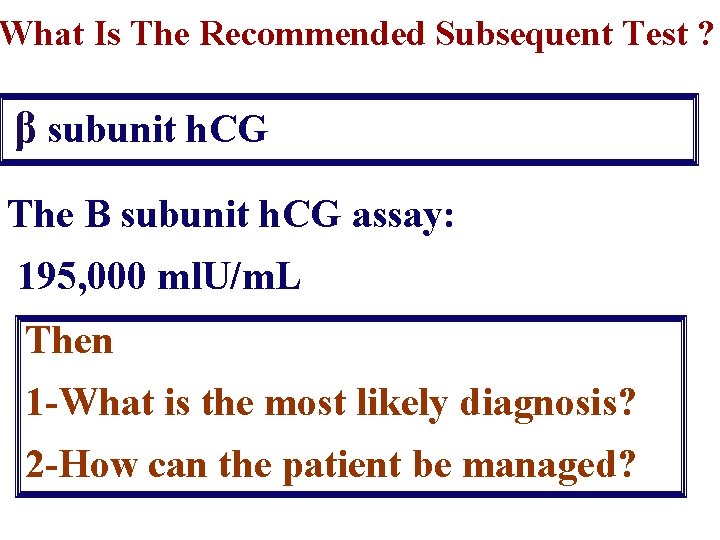

What Is The Recommended Subsequent Test ? β subunit h. CG The B subunit h. CG assay: 195, 000 ml. U/m. L Then 1 -What is the most likely diagnosis? 2 -How can the patient be managed?

1 -What Is The Most Likely Diagnosis? The snowstorm pattern on U/S& The abnormally high h. CG level are diagnostic of Vesicular Mole Probably complete V. mole

Why It Is Probably Complete V. Mole? It demonstrates the typical U/S appearance of complete V. mole : a complex, echogenic intrauterine mass containing many small cystic spaces. Fetal tissues and amnionic sac are absent However the final differentiation is after histopathology.

What Is The Plan of Management? There are 2 important basic lines : 1 -Evacuation of the mole 2 -Regular follow-up to detect persistent trophoblastic disease If both basic lines are done appropriately, mortality rates can be reduced to zero.